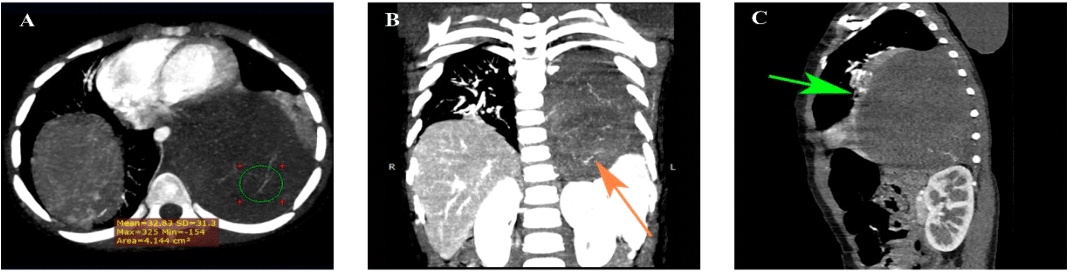

Three-year-old girl with no significant personal or family history, attended with her father, who reported that the patient presented clinical symptoms characterized by pain in the mesogastrium since 6 months ago, to which she did not pay attention, a week ago the pain intensified accompanied by nausea that did not lead to vomiting. On physical examination, on deep palpation in the mesogastrium there is evidence of a mass of hard consistency, well-defined borders of approximately 3cm in diameter, non-mobile. An abdominal ultrasound was sent and reported a complex mass in the pancreas, round edges, slightly heterogeneous content, negative Doppler, measuring 8.9x7.9x9.6cm. Due to limited resolution capacity, the patient was referred to a more complex health care facility, and the clinical picture was accompanied by a wet cough and an unquantified thermal rise. Chest X-ray reports blurring of the left costo-diaphragmatic angle, blurring of the cardiac silhouette due to the presence of radiopacity in the left hemithorax (Figure 1). CT Scan of the Chest with Contrast and upper abdomen shows a solid mass that captures contrast and with vessels inside, located in the left pleural cavity measuring 8.1cm x 11.2cm x 8.2 cm (width x height x depth) with a volume of approximately 387cc (Figure 2). Due to the complexity of the lesion she was referred to pediatric cardiothoracic surgery where she underwent exploratory thoracotomy obtaining a complete exeresis of the mediastinal mass without complications. A sample was sent for histopathological study which was compatible with ganglioneuroma. The patient was continuously monitored in the pediatric intensive care unit and was successfully discharged after 15 days.

Figure 2 CT Scan of the chest with intravenous contrast media. (A) Axial: In the left lung field there is a homogeneous solid mass of well-defined smooth contours, with heterogeneous enhancement, without contrast medium has an attenuation of 40 HU, there are several visible vessels inside the lesion that appear to depend on intercostal and aortic branches, after the application of contrast medium increases between 10 and 20 HU of attenuation. (B) Coronal: It is located between vertebral levels T3- T11, measuring 8.1cm x 11.2cm x 8.2 cm (width x height x depth) with a volume of approximately 387cc, caudally causes descent of the left diaphragm inferiorly displacing the left spleen, adrenal gland and kidney. (C) Sagittal The mediastinal mass forms acute angles with the parietal pleura and displaces anteriorly the middle mediastinal structures. In addition, it causes left lower lobar atelectasis (green arrow). The mass contacts the descending aorta, esophagus and pericardium, but maintains preserved cleavage planes.